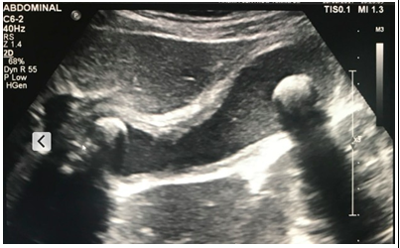

Uma mulher de 42 anos, obesa, com queixa de dor no epigastro e hipocôndrio direito irradiada para o dorso há três dias, que piora com alimentos gordurosos. Relata ainda náuseas e vômitos associado ao quadro. Nega febre e outros sinais e/ou sintomas. Ao exame: bom estado geral, temperatura axilar de 37 ºC; frequência cardíaca de 90 BPM. Pressão arterial 120x70 mmHg. Abdome flácido, doloroso à palpação em hipocôndrio direito. Sinal de Murphy positivo. O médico do pronto-socorro pediu uma ultrassonografia de abdome conforme a imagem a seguir.

De acordo com o quadro clínico e o exame complementar, qual a alteração ultrassonográfica e o tratamento para esta paciente?